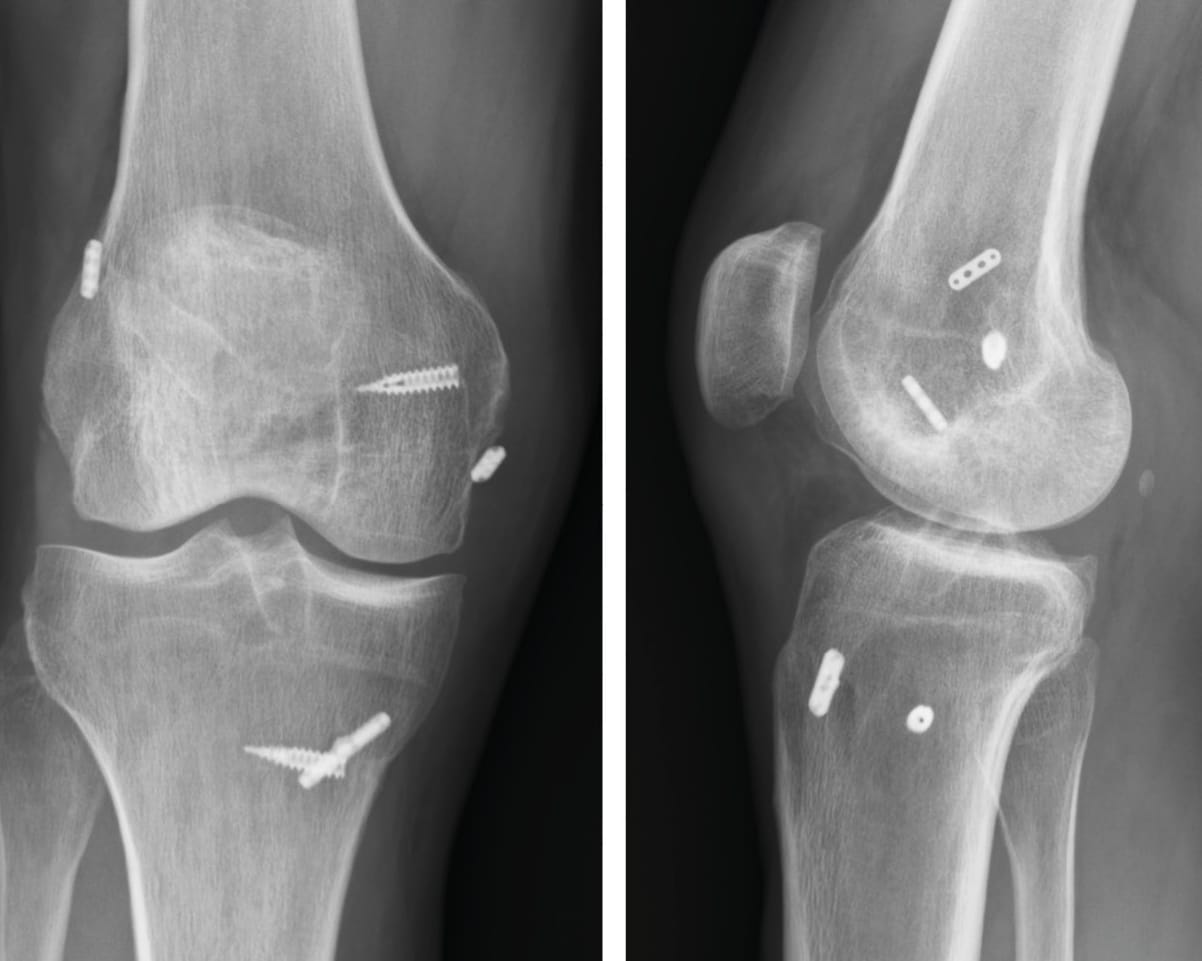

Coin de l'interne Planification chirurgicale et organisation de la prise en charge des lésions multi-ligamentaires du genou , Nicolas Bouguennec Hôpital Privé Sévigné, 3, Rue du Chêne Germain, 35510 Cesson-Sévigné, France , Antoine Morvan Clinique du Sport Bordeaux Mérignac, Bordeaux, France , Nicolas Graveleau Clinique Paris V, 36 boulevard Saint-Marcel, 75005 Paris N°329 - Décembre 2023 ● 16 min de lecture